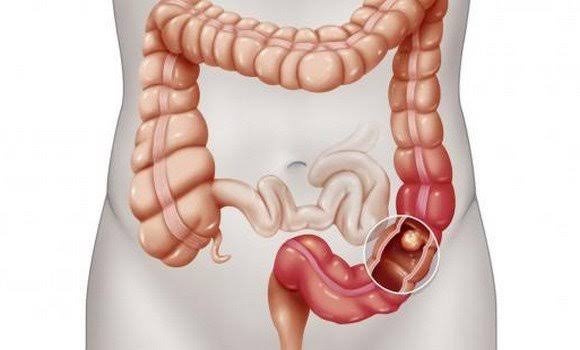

تعتمد توقعات الحياة على مدى تغلغل الورم الخبيث في جدار الأمعاء، وفي المرحلة 2a يؤثر المرض على جدار الأمعاء كله، لكنه لا يتجاوزه، ويمكن فصل موطن الورم بوضوح عن الأنسجة المحيطة، ما يزيد من فعالية العلاج الجراحي.

في المرحلة b2، من الممكن ينتقل الورم إلى الأعضاء المجاورة - الكبد، والمثانة، والرحم لدى النساء.

يعتمد التشخيص والعلامات السريرية لسرطان القولون والمستقيم في المرحلة 3، على حجم الورم وموقعه في جدار القولون مع عدد ومكان الغدد الليمفاوية المصابة.

في المرحلة 3a، يصل الورم إلى حجم صغير ويقع بشكل أساسي في تجويف الأمعاء، ولا يؤثر على الأعضاء المجاورة.

تتميز المرحلة التالية، 3b، بحجم الورم الكبير وانتشاره الأكثر شراسة على طول الجدار إلى الأمعاء وأعضاء تجويف البطن.

في المرحلة الربعة من سرطان القولون يتم اكتشاف الإصابة في المناطق البعيدة من الجسم، مثل الكبد، والتي يتدفق من خلالها الدم من أجهزة تجويف البطن والحوض الصغير.

وتظهر بقع ورمية بشكل أقل في الرئتين، والأعضاء التناسلية، والعظام، والبنكرياس، والغدد الكظرية.